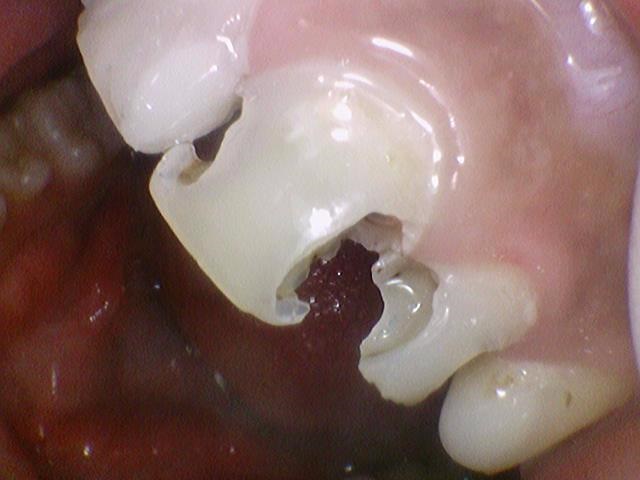

충치를 제거했더니 남는 치아부분이 이렇게 밖에 없는 상태ㅠㅠ

20대 환자분인데도 어떻게 이런 앞니로 학교다니고 사회생활 하셨냐며...

대문이 2개는 신경치료하고 앞니 크라운 2개 하셔서 2개는 크라운까지 완성된 상태구요.

사진상 오른쪽(환자분 기준으로는 왼쪽) 두번째 치아는 아직 크라운을 못하시고

신경치료 하고 사회생활은 하셔야하니 현재 레진으로 만들어놓은 임시 상태인데

환자분이 시간이 없이 너무 바쁘셔서 일단 다음번에 크라운 작업 시작하기로 한 상태입니다.

어쨌든 사회생활은 하실만큼 만들어놓은 상태죠.